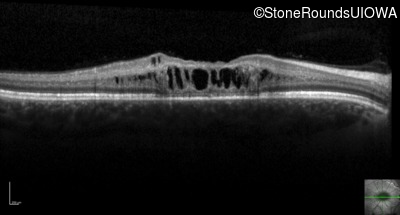

Optical Coherence Tomography - Right - 20/80 sc

Exemplar / OCT Stack